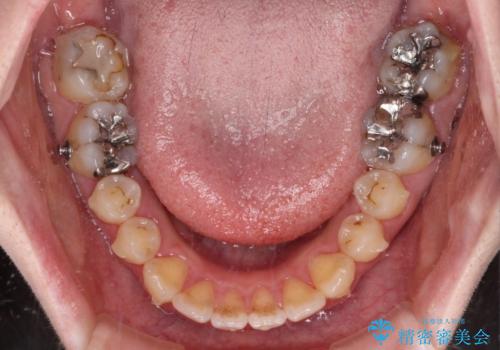

- 捻れた前歯が飛び出しており、口が閉じにくいとのことで来院された患者様です。

出っ歯というわけではないものの、前歯の捻転により口唇が押し出されている状態でした。

親知らずを抜去し、歯列全体を後方に移動させつつ、IPR(歯と歯の間を削る)でスペースを獲得し、インビザラインを用いて叢生を解消しながら前歯の突出を改善することとしました。

インビザラインは、患者様の協力無しには成立しない治療ですが、しっかりと装着時間を遵守してくださり、1年弱で治療を終えることができました。